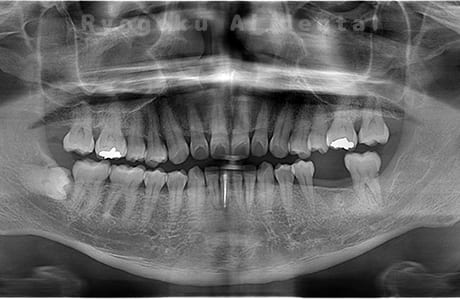

Case07

-

- 原因

- 右下6番歯根破折

- 治療内容

- インプラント治療

- 治療費用

- 約600,000円

右下の腫れが治らないとの事でご来院された患者様です。歯が割れていたため、抜歯を行い、骨に代わるお薬を入れ、インプラントを埋入致しました。経過良好で大変満足していただけました。

<リスク・副作用>

治療後、痛みや違和感、出血、腫れなどが出る事があります。喫煙者、糖尿病などの方の場合、歯が生着しない場合があります。